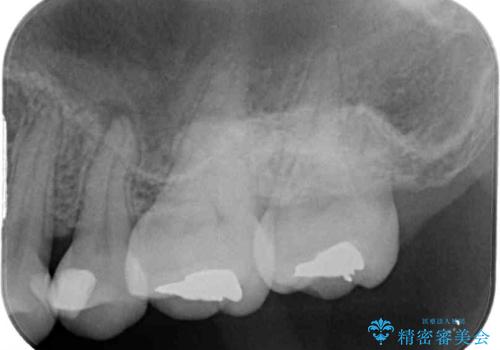

- 近医にてむし歯治療を行った後に痛みが出たとのことで来院された患者様です。

左下奥歯は術後から咬合時の痛みが発現し、来院時には脈を打つような痛みが認められました。

診察の結果、神経を取り除く必要があると判断されたため根管治療を行いました。

その後、左上の奥歯にも咬合時の痛みが認められ、レントゲン写真より歯内の神経が失活していることが分かりました。

2歯ともに根管治療を行い、その後はオールセラミッククラウンにて補綴治療を行うこととしました。